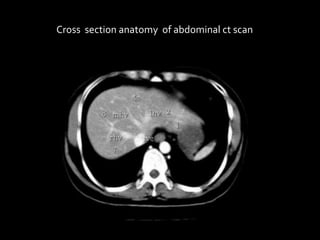

Cross section anatomy of abdominal ct scan

Anatomy of the liver segments

Cross section anatomyof abdominal ct scan

Anatomy of theliver segments